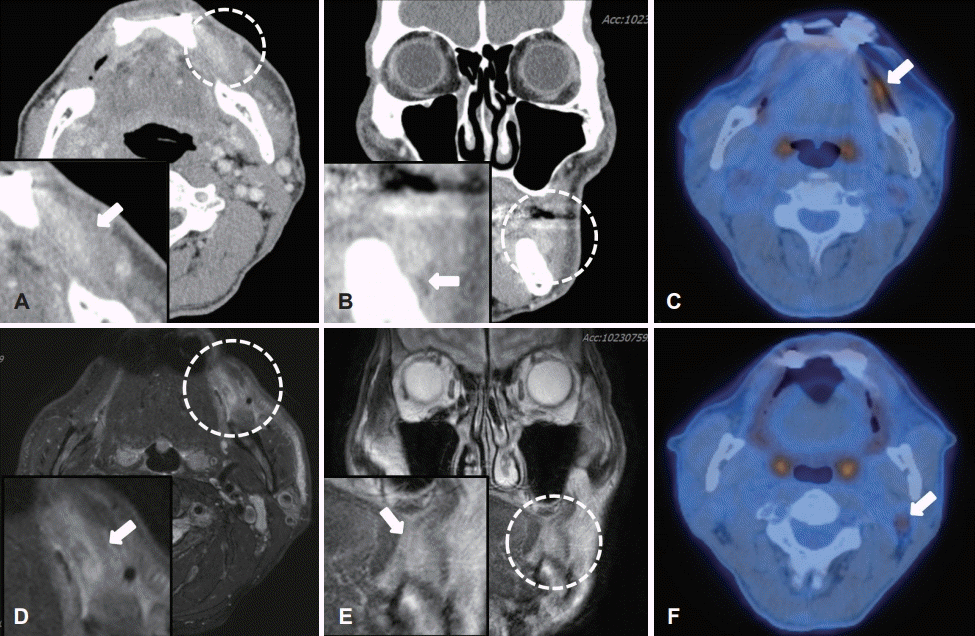

병변의 위치와 깊이, 주변 조직으로의 침범 정도를 보다 정확하게 평가하기 위해 수술 전 시행한 경부 컴퓨터단층촬영(CT) 및 경부 자기공명영상(MRI) 검사에서 좌측 볼 점막 부근에 2.1×0.8 cm 크기의 다소 경계가 불명확하고 불균질한 음영을 보이는 종물이 관찰되었다. CT 검사에서 하악골에 인접한 소견이 보였으나 골 침범의 가능성은 낮아 보였고, MRI 검사를 통해 협근(buccinator muscle)을 비롯한 주변으로의 침범 정도를 확인하고자 하였으나 불균질한 신호강도를 보여 주변 연조직과의 침범 여부를 가늠하기에는 다소 제한점이 있었다(Fig. 2A-D). 원격전이 여부를 확인하기 위해 PETCT를 시행하였으며 좌측 볼 점막의 병변에서 높은 흡수 섭취를 보여 malignancy 가능성을 시사하였으며, 좌측 경부 림프절 2구역에서 경도의 흡수 섭취를 보였으나 반응성 림프절 소견으로 의심되었다(Fig. 2E and F). 수술 전 시행한 혈액검사, 심전도 및 소변검사에서 모두 정상 범위 소견을 보였으며, 흉부 방사선 검사에서 좌측 늑막의 농밀화 혹은 좌측 흉수 소견을 보여 호흡기내과 전문의의 협의진료하 수술적 치료를 시행하기에 문제가 없음을 최종 확인하였다.

Preoperative diagnostic imaging. Preoperative axial, coronal view of enhanced neck CT & neck MRI scan shows the ovoid, ill defined, measuring 2.1 cm in longest dimension, heterogenous enhanced mass (arrow) in the left buccal area (A-D). Preoperative axial view of PET-CT scan shows hypermetabolic mass in left buccal mucosa (arrow above) seemed to be malignancy more likely and mild hypermetabolic LN in left neck level II area (arrow below) seemed to be reactive lesion (E, F).